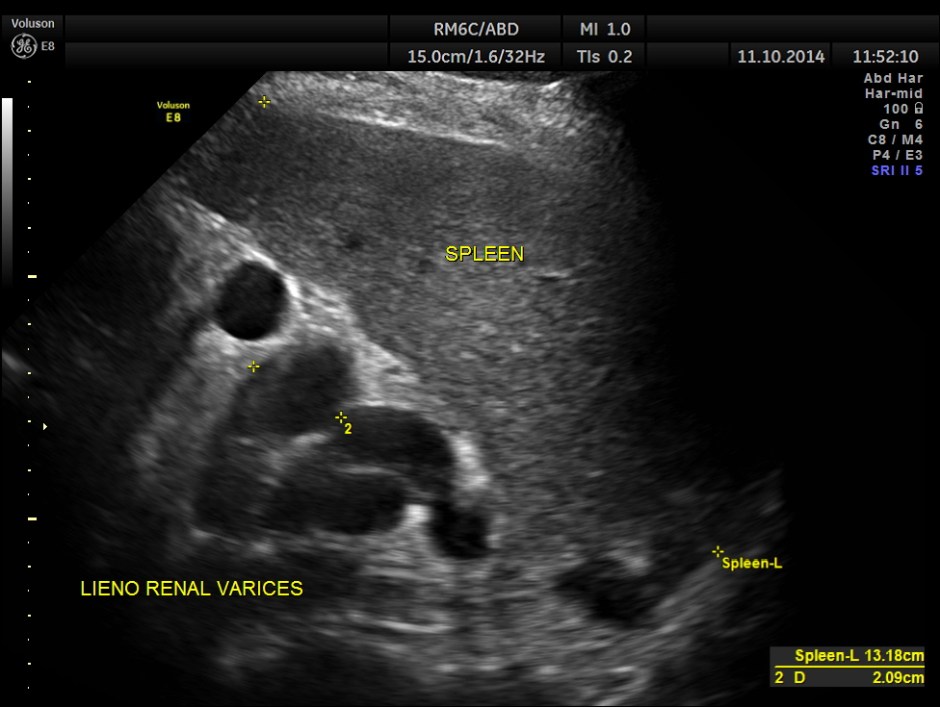

Variceal dilatation of vessels in the lieno renal ligament. Splenomegaly is also seen.

The spleno portal vein is just mildly dilated.

Ultrasonically a diagnosis of Portal fibrosis with portal hypertension – splenomegaly and lieno renal varices was given.